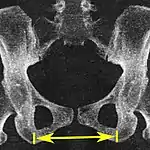

Interspinous distance

Axial plane

The line between the closest bone points of the ischial spines 9.5 to 11.5 cm.[6]